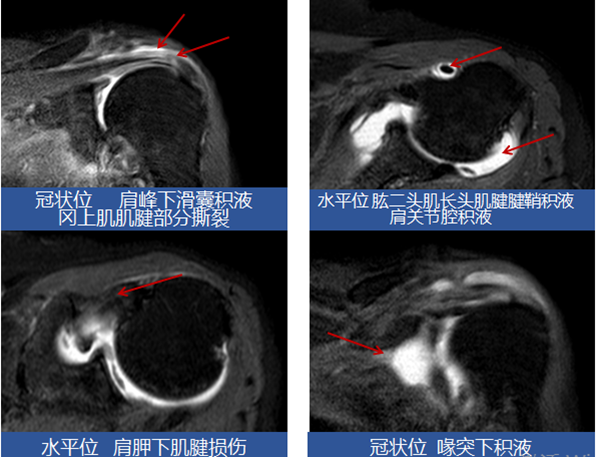

74岁的朱女士于2月余前诊断为脑干梗死,在老家医院康复科住院治疗,1月余前左肩出现疼痛伴关节活动度受限,继续在该医院治疗无效后经多方打听患者入住我科进一步治疗。入院后经专科查体及辅助检查后考虑该患者为肩关节半脱位合并肩袖损伤、左侧肱二头肌长头肌腱腱鞘炎。诊断明确后为该患者制定康复目标(强化左侧肩关节稳定性、缓解左肩关节疼痛、提高肢体实用性)。并根据该目标为患者制定了个体化康复治疗方案。经一个疗程的治疗,患者左肩关节疼痛较前减轻,夜间睡眠质量也得到改善,左上肢实用性有所提高,可以拿馒头送到嘴里,达到患者目标,出院回家。回家1周后患者家属很开心的给我发来消息,王医生,你看,我姐在跟邻居打扑克牌(要知道患者之前拒绝出门见人),这一刻,我再次理解了我工作的意义。

肩关节半脱位、肩峰撞击综合征、肩手综合征、痉挛/挛缩/粘连性关节炎、周围神经病变、肩袖损伤、肱二头肌长头肌腱腱鞘炎。

包括疼痛性质评价、肩关节外观、肩关节活动、肩部超声、肩关节磁共振、心理评估。